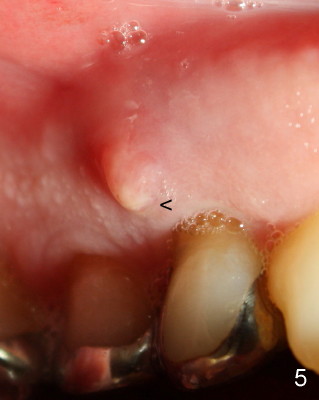

A 68-year-old male patient presented to office in March 2011 with chief complaint "upper right tooth is not comfortable". Clinical exam shows missing teeth: #13,14,30, and 31, replaced by removable partial dentures. The tooth #5 has mild mobility and percussion. Pocket depth is within normal limit. X-ray shows no significant finding (Fig.1,2). Three months later, he returned with chief complaint "The tooth has swelling". It appears that there is exostosis on buccal aspect of upper teeth. There is no erythema or tenderness on buccal mucosa around the tooth #5). But X-ray shows periradicular radiolucency (arrowheads in Fig.3,4). Cone Beam CT was recommended to confirm diagnosis of root fracture. Approximately one month later, abscess developed with fistula formation. Symptoms were controlled by taking Amoxicillin. On August 2, 2011, the patient returned for prophylaxis. The fistula was present (arrowhead in Fig.5). Gutta percha #30 was inserted into the fistula. PA was taken. The point of the gutta percha (blue arrowhead in Fig.6) points to enlarged periradicular radiolucency (black arrowheads). Deep pockets were in distobuccal and lingual. Decision was made to extract the tooth. Fig.7 shows the socket immediately extraction. The buccal plate is perforated. The septum (*) is not intact. Cracking sounds were heard during extraction. In fact the lingual root is obliquely fractured with exposed post (Fig.8: *). There is another cracking line from the buccal root to the lingual one (arrowhead). In brief, the earliest sign of root fracture is nonspecific. It should alert us to its suspicion.